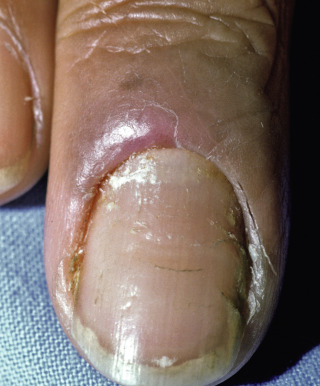

Chronic paronychia is a persistent inflammatory disorder of the proximal nail fold. It affects chiefly women, but both genders and any age group may be affected. It presents as erythema and edema of the proximal nail fold, with loss of the cuticle ( Figs. 25.3 and 25.4 ). The nails may be normal but often demonstrate excessive ridges (Beau lines), variable onycholysis, other nail irregularities, or even a green-blue discoloration due to Pseudomonas infection.

Fig. 25.3

Patient with chronic paronychia, with dystrophic nail.

(From the Fitzsimons Army Medical Center Collection, Aurora, CO.)

Fig. 25.4

Patient with chronic paronychia, with superficial peeling (onychoschizia) of nails.